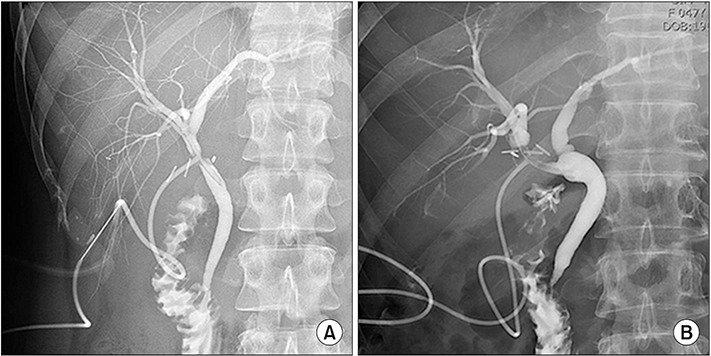

This report describes the laparoscopic end-to-end biliary reconstruction with T-tube for transected bile duct injury (BDI) during laparoscopic cholecystectomy.

Between January 2014 and December 2017, 2,901 patients underwent laparoscopic cholecystectomy at a single institution. Among them, 8 patients experienced a transected BDI during laparoscopic cholecystectomy, so the surgeon performed laparoscopic end-to-end biliary reconstruction with T-tube. Our patient series consisted of 6 women (75%) and 2 men (25%) with a mean age of 48.3 years (median, 49 years; range, 29-77 years). Two cases were converted to open surgery. The most common injured site was the common bile duct (5 of 8, 62.5%). The most common injury type, using Bismuth's classification system, was type I (3 of 8, 37.5%). The mean operating time was 136.8 minutes (median, 135.0 minutes; range, 0-180.0 minutes). The mean hospital stay was 7.0 days (median, 4.5 days, range: 3.0-21.0 days). The mean follow-up was 36.4 months (median, 34.0 months; range, 16.0-63.0 months). We observed one postoperative complication during the follow-up period. The patient had an anastomosis site leakage and was cured after reoperation.

Laparoscopic end-to-end biliary reconstruction with T-tube for transected BDI during laparoscopic cholecystectomy seems to be safe and feasible in selected patients. However, long-term follow-up to identify complications from bile duct stricture remains important.